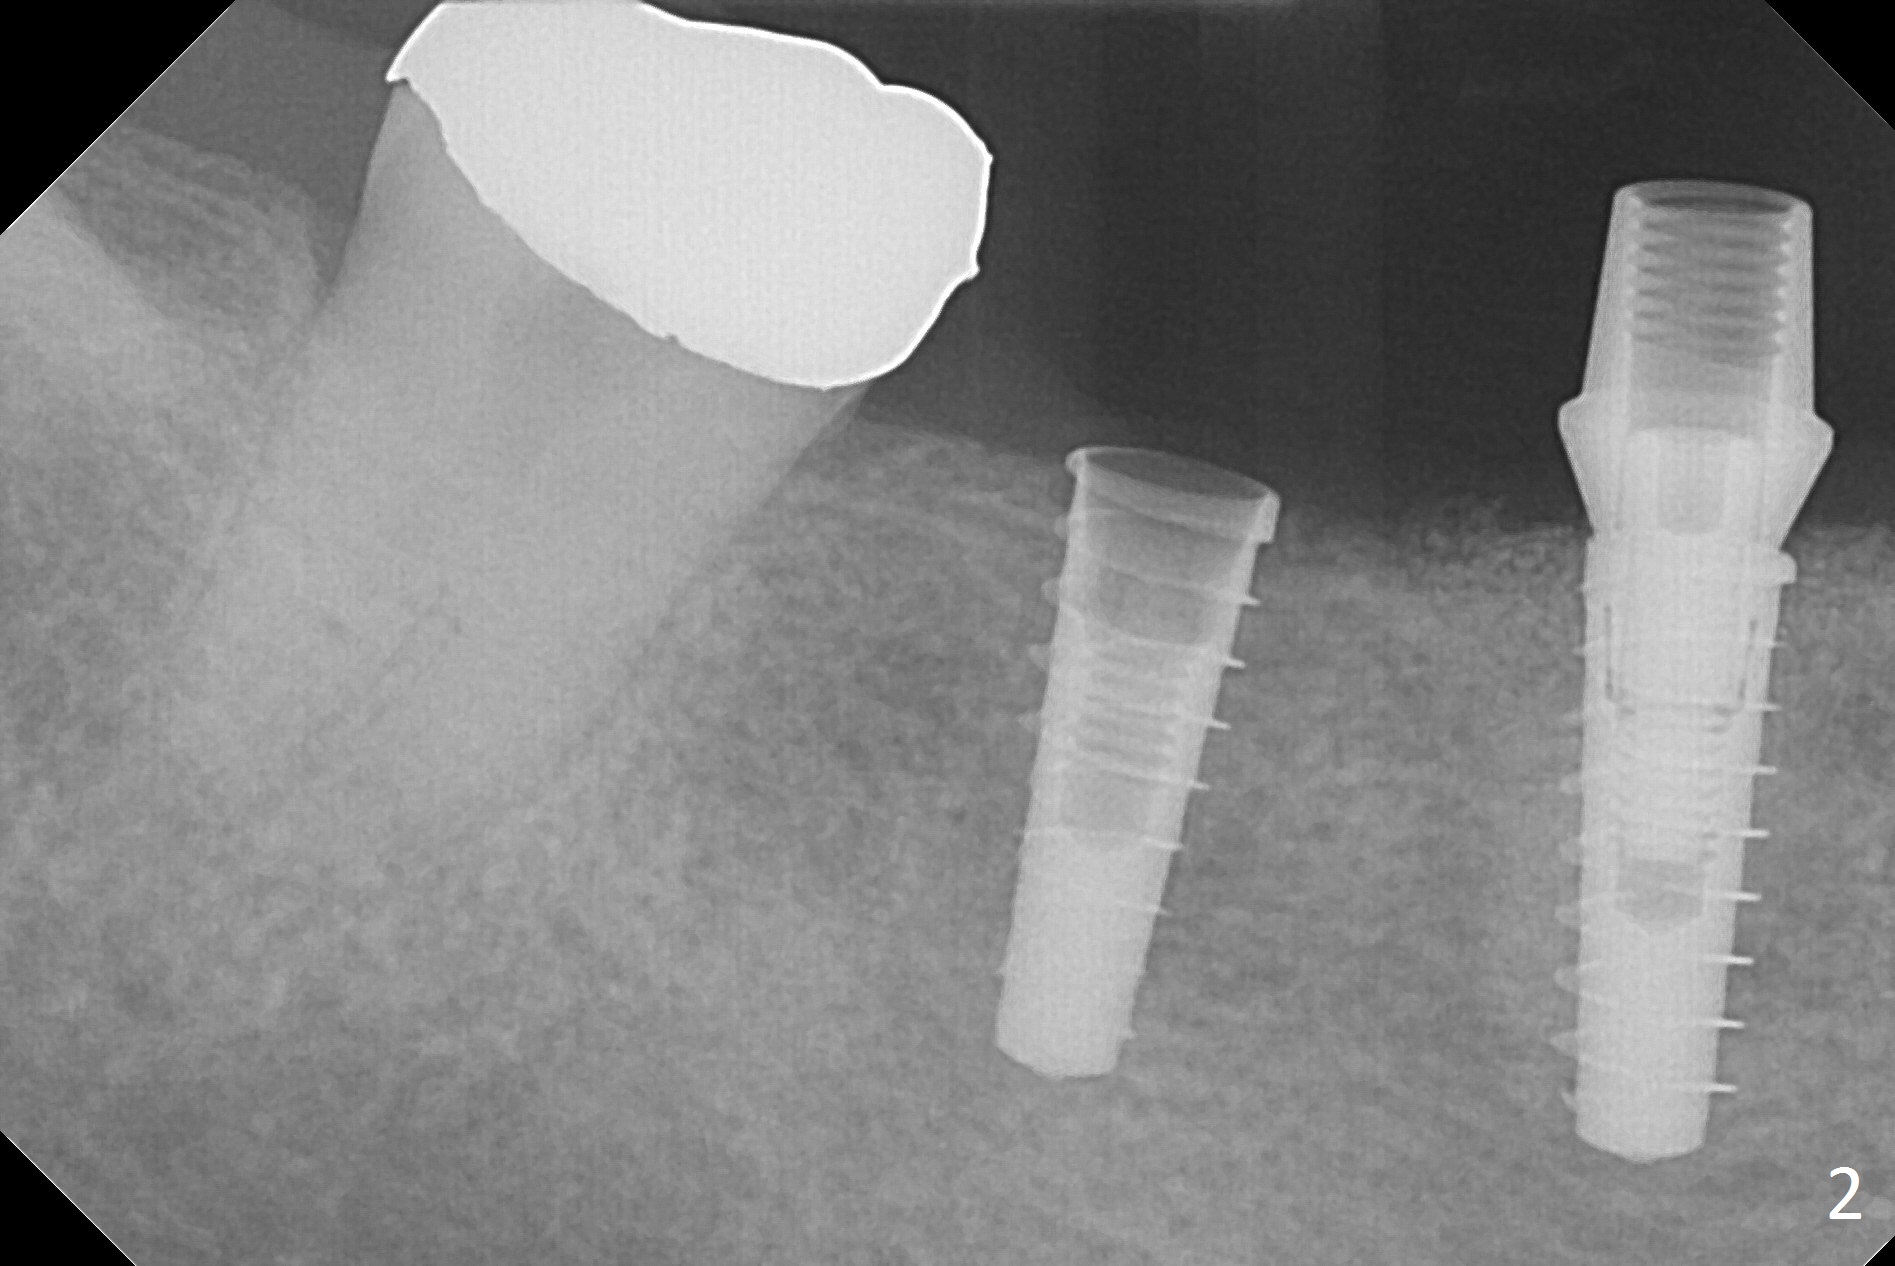

After incision, the ridge at #29 and 30 is found ~ 5 mm wide buccolingually. To place a 4x11 mm IBS implant at #30, the ridge is expanded using BEB technique (bone expansion and bending, Fig.1). It appears that the initial osteotomy at #29 is mesial (Fig.1 yellow dashed line: the distal surface of the root of the tooth #28). After moving the osteotomy distal, the final implant position at #29 (4x11 mm) is within normal limit (Fig.2). The bone at #29 seems to be not so dense that bending (using 1.6 mm drill) is not necessary (using Magic Split and Magic Expanders 3 and 3.8 mm). Later the implant at #30 (4x11 mm) is placed deeper (Fig.3). After placing bone graft around the implants/abutments and suturing, the ridge looks wider with apparent formation of the gingival bands around the abutments (Fig.4 *). Three months and a half postop, bone loss is minimal (Fig.5) and gingival bands forms around the abutments (Fig.6). Fig.7 is taken 1 month post cementation (panoramic X-ray). The patient chews normally 1 year (Fig.8) and nearly 2 years (Fig.9,10) post cementation. The crown at #31 needs recementation 2 years 7 months post #30 cementation; the incomplete seating of the abutment was noted for the first time (Fig.11). Five months later the patient is going to be retired and wants to travel abroad. After approval, the access hole was reopened; articulating paper shows under occlusion of the crown (Fig.12). Since the gap between the abutment and the implant is large, the abutment/crown complex seems to be necessary to be turned (Fig.13 curved arrow). The proximal surfaces of the crown need to be trimmed (straight lines). After turning, the crown sits down with screw tightening; the patient feels pain from the gingival cuff (Fig.14). After turning, the abutment appears to be completely seated (Fig.15). In fact the mesial and distal surfaces of the crown should have clearance from the neighboring teeth (Fig.14) so that pick-up impression is able to hold the crown/abutment complex securely (Fig.16: *). The crown is separated from the abutment after crown repair. They are seated together (loose connection) using the crown as a guide to seat the abutment. BW is taken without the crown. It appears that the abutment remains seated completely (Fig.17). The apical space is equal between #29 and 30 (Fig.17, as compared to Fig.5).